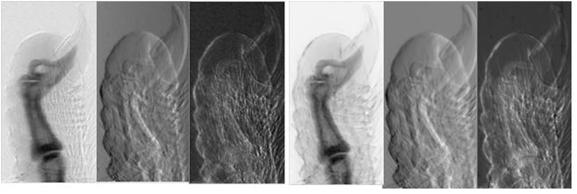

图6. 同步辐射多种成像方法比较,(a) 豚鼠耳蜗吸收衬度成像,(b) 豚鼠耳蜗同轴相位衬度成像,(c) 豚鼠耳蜗衍射增强相位衬度成像。豚鼠耳蜗对声音非常灵敏,豚鼠耳蜗与人耳蜗相似,是耳科专家研究听力的好材料。豚鼠耳蜗样品由首都医科大学提供。

图7 鱼成像比较,(a) 吸收衬度成像,(b) 衍射增强相位衬度成像。从两幅图像的比较,可以显示相位衬度成像可以获得比吸收衬度成像高得多的衬度。